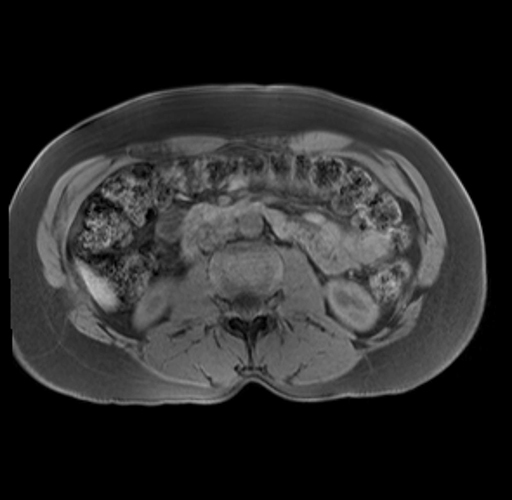

Imaging Analysis

Look through the patient's CT scan to identify any areas of concern for the necessary procedure.

Based on your CT findings, which issue(s) are present and would give reason for "planned slowing down moment(s)" in this case?